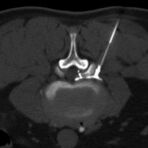

Wirbelsäule

• Darstellung von Frakturen, Tumoren und Bandscheibenveränderungen

Interventionelle Eingriffe

Durchführung am Standort im Diakonissenkrankenhaus

• z. B. Punktionen zur Gewebsentnahme

Schmerztherapie

(dazu mehr auf der Seite Schmerztherapie)

Der Multislice-Scanner ermöglicht eine dem aktuellen Stand der Technik entsprechende, leitliniengerechte diagnostische Untersuchung sämtlicher Körperregionen. Darüber hinaus gestattet der neue Computertomograph auch eine für Arzt und Patient bequeme Durchführung CT-gestützter Interventionen wie z.B. Schmerztherapien der Wirbelsäule.